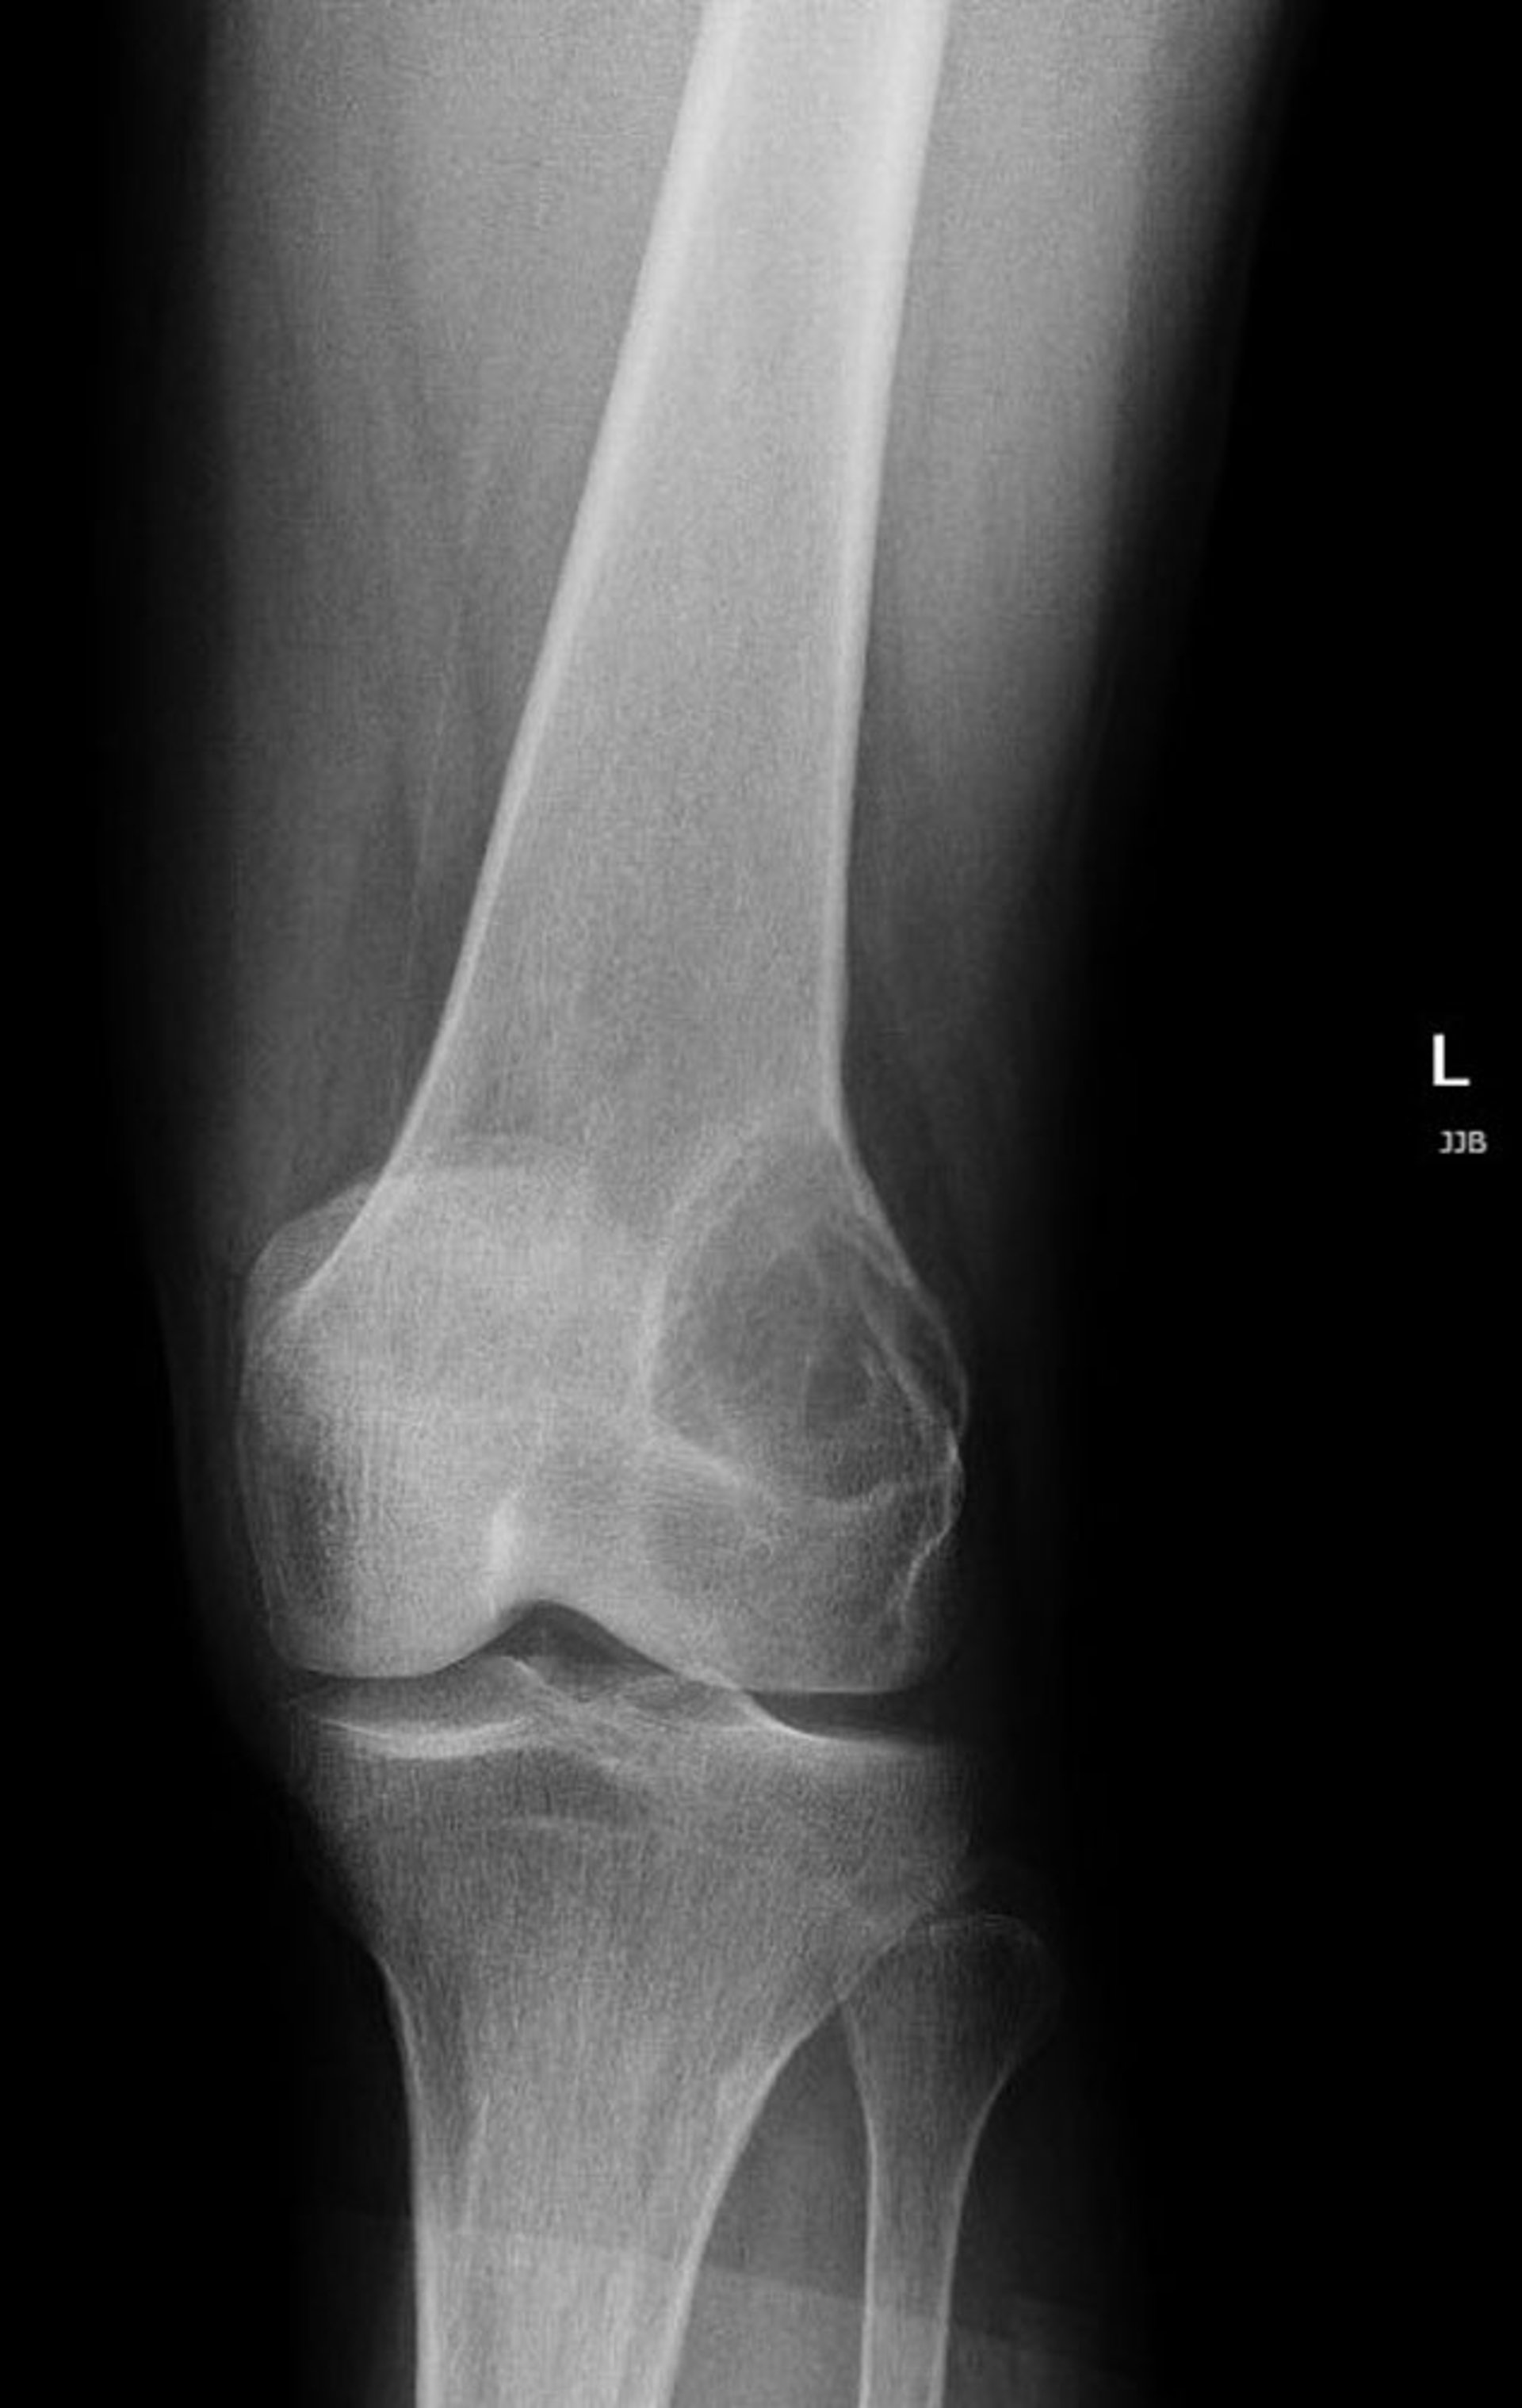

Riesenzelltumor des Knochens

Diese Röntgenaufnahme des Knies zeigt eine strahlendurchlässige Läsion im lateralen distalen Femur über dem Knie, die für einen Riesenzelltumor des Knochens charakteristisch ist.

Image courtesy of Lukas Nystrom, MD.